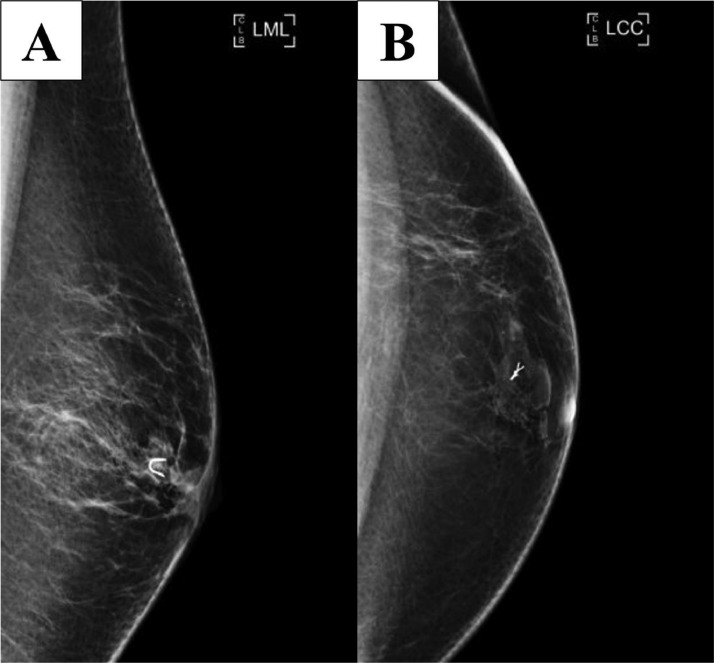

Bilateral diagnostic mammograms (craniocaudal and mediolateral oblique; see Fig. 1) were obtained and revealed 1 round mass with mostly circumscribed margins and another round mass with obscured margins and associated coarse calcification in the left anterior breast subareolar region 3:00 position in the area of palpable concern.

Fig. 1.

Bilateral craniocaudal (A) and mediolateral oblique (B) mammograms show 1 round mass with mostly circumscribed margins and another adjacent mass with obscured margin and with associated coarse calcification in the left breast subareolar region. BB markers are placed on the nipples and a triangular marker is placed on the area of palpable concern.

Ultrasound-guided core biopsy was performed (Fig. 2), and a biopsy clip was placed (Fig. 3).

Fig. 3.

Left mediolateral (A) and left craniocaudal (B) postbiopsy mammograms show the clip in the appropriate position.